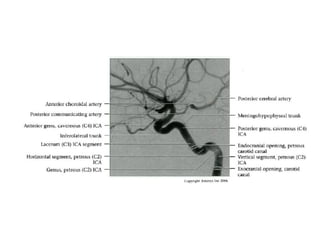

INTRACRANIAL INTERNAL

CAROTID ARTERY

Overview

• Complex course with several vertical /

horizontal segments, 3 genus (one

petrous, two cavernous)

• Six intracranial segments (Cervical lCA =

C1):

- Petrous (C2), Lacerum (C3),

Cavernous (C4), Clinoid (C5),

Ophthalmic (C6), Communicating (C7)

Cavernous (C4) segment

• Three subsegments joined by two genus (knees)

- Posterior vertical (ascending) portion

- Posterior (more medial) genu

- Horizontal segment

- Anterior (more lateral) genu

- Anterior vertical (subclinoid) segment

• Covered by trigeminal ganglion posteriorly

• Abducens nerve (CN6) is inferolateral

• Major branches

- Meningohypophyseal trunk (arises from posterior

genu, supplies pituitary, tentorium and clival dura)

- Inferolateral trunk arises from horizontal segment,

supplies cavernous sinus (CS) dura / cranial nerves;

anastomoses with ECA branches through foramens

rotundum, spinosum, ovale

Communicating (C7) segment

• Extends from below PCoA to terminal lCA bifurcation

into anterior cerebral artery (ACA), middle cerebral artery

(MCA)

• Passes between optic (CN2), oculomotor (CN3) nerves

- Posterior communicating artery

- Anterior choroidal artery (courses posteromedial,

then turns superolateral in suprasellar cistern; enters

temporal horn at choroidal fissure; supplies choroid

plexus, medial temporal lobe, basal ganglia,

posteroinferior internal capsule)